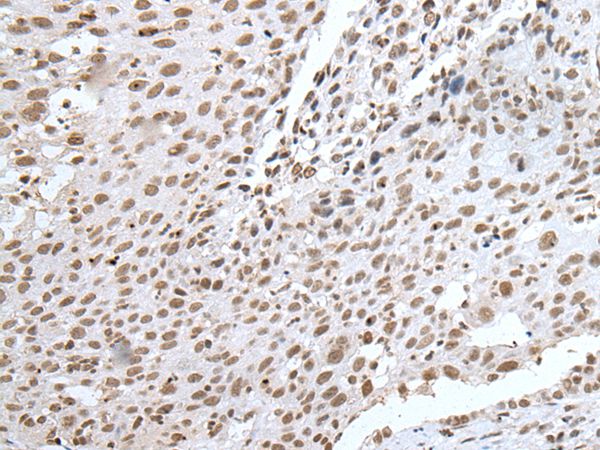

The image on the left is immunohistochemistry of paraffin-embedded Human lung cancer tissue using RBM8A Antibody at dilution 1/30, on the right is treated with fusion protein. (Original magnification: x200)